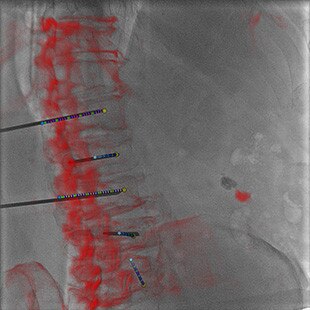

INTERVENTIONS AU NIVEAU DU RACHIS

Guider